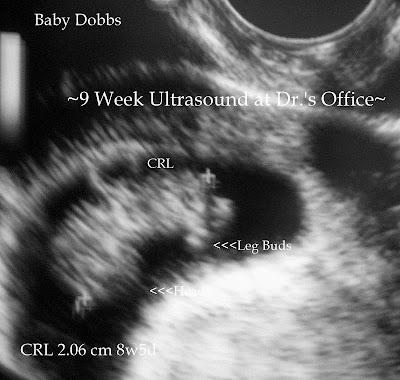

~Dr.'s Office Visit 9-24-08~

I met Dr. Mckenzie for the first time today. I wasn't extremely impressed if I am going to be honest. I waited 3 hrs for an Ultrasound & to be weighed. I could have done that myself at work! I did't even get bloodwork. He is a nice guy, but I just don't think he is right for me. I didn't think it would matter that much who I saw, but I just want to be completely comfortable because, I am a worrier already & just want everyhting to go smoothly. But the good news is he said everything was on track & looking good. So that gave me some peace for the time being, now I am just on the search for a new Doc.